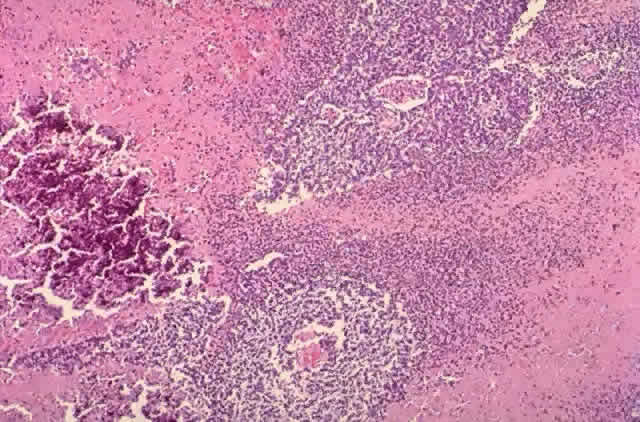

The cells tend to have large basophilic nuclei with little cytoplasm. Numerous mitoses and areas of necrosis with calcification are characteristic (Fig. 4). The rapidly growing tumor outstrips its blood supply. Cuffs of cells surround blood vessels. Viable cells may be found in the vitreous or subretinal space. Important pathologic findings affecting survival include extrascleral extension, choroidal invasion greater than 3 mm2, and optic nerve involvement.88

Fig. 4. Retinoblastoma (H & E, × 25)